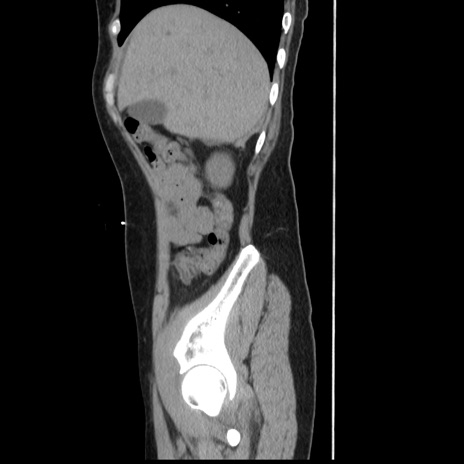

症例10(矢状断像)

【症例】 50歳代女性

【主訴】 腹痛

【現病歴】前日生レバーを食べた。今朝に排便あり。 昼前に突然発症の腹痛を生じ、当院救急外来を受診した。

【既往歴】 子宮筋腫にてで子宮全摘後

【身体所見】 意識清明、腹部:平坦、軟、下腹部やや左を中心に圧痛・反跳痛あり、筋性防御あり

【データ】WBC 7800、CRP 0.07